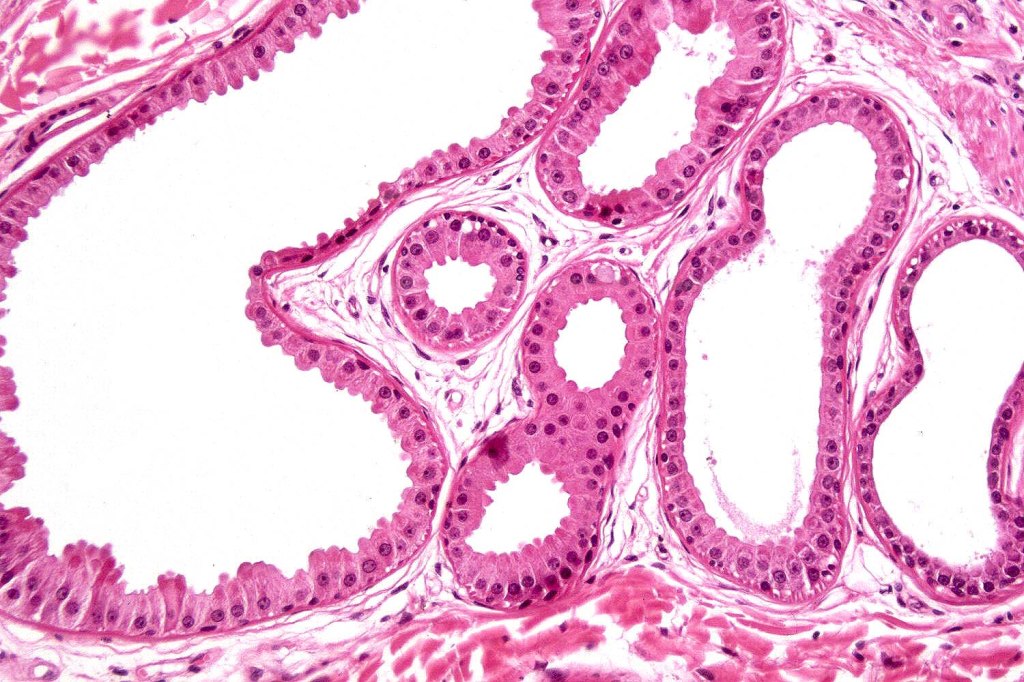

•Trichogerminoma is a distinctive variant being composed of tumor nodules with basaloid cells surrounding pale or eosinophilic micronodules (Zellballen)

•Panfolliculoma represents an often-cystic trichoblastoma showing differentiation toward all follicular elements